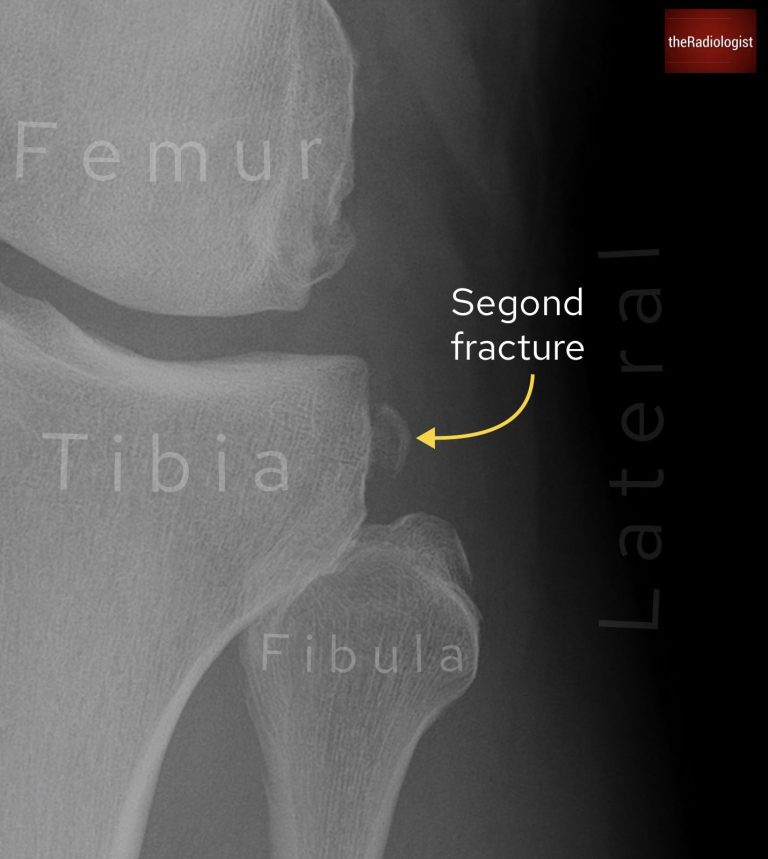

A Segond fracture is another sign of an ACL injury, here you are looking for a bone fragment lateral to the lateral tibial plateau, above the fibula head and just below the joint line.

If you see a bone fragment above the fibula this could represent a Segond fracture which is a sign of an ACL injury.

KEY POINT

A lateral tibial plateau avulsion fracture is known as a Segond fracture and is a sign of an ACL injury.